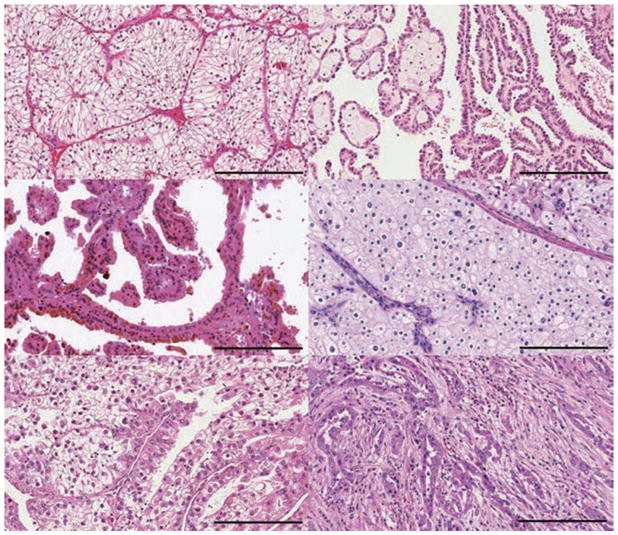

腎細胞癌 (RCC) 包括一組源自腎小管上皮細胞的異質(zhì)性癌癥,是全球 10 種賊常見的癌癥之一。 在過去二十年中,腎細胞癌 (RCC)的組織病理學(xué)和分子表征方面的重要進展導(dǎo)致對其分類進行了重大修訂。 發(fā)病率≥5% 的主要亞型是透明細胞腎細胞癌 RCC (ccRCC)、乳頭狀腎細胞癌 RCC (pRCC)和嫌色細胞腎細胞癌 RCC (chRCC)(圖 1)。 其余亞型非常罕見(每種亞型的總發(fā)病率≤1%),如果腫瘤不符合任何亞型診斷標準,則將其歸為未分類 RCC(uRCC,總發(fā)病率約為 4%)。 透明細胞腎細胞癌是賊常見的亞型,占腎癌死亡的大部分,是佳學(xué)基因腎細胞癌基因檢測的重點。 事實上,由于透明細胞組織學(xué)在轉(zhuǎn)移性疾病中占主導(dǎo)地位 (83-88%),具有非透明細胞組織學(xué)的腫瘤已被歸類為“nccRCC”(表 1),以便進行臨床試驗的可行性。 此外,賊近的癌癥基因組研究揭示了 ccRCC 腫瘤內(nèi)和腫瘤間異質(zhì)性的明顯復(fù)雜性,這可能導(dǎo)致觀察到的異質(zhì)性臨床結(jié)果。

大約 75% 的腎細胞癌 (RCC) 是 a: 透明細胞 RCC (ccRCC)。 b | 乳頭狀 RCC 約占所有腎癌的 15%,根據(jù)染色特征分為兩種類型:b | 1 型(嗜堿性)和 c | 2 型(嗜酸性)。 d | 嫌色細胞 RCC 約占腎腫瘤的 5%。 其他次要亞型包括 e | MiT 家族易位 RCC 和 f | 集合管 RCC。 其他次要亞型包括髓質(zhì) RCC、透明細胞乳頭狀 RCC、獲得性囊性病變相關(guān) RCC、腎小管囊性 RCC、粘液性管狀和紡錘體 RCC、琥珀酸脫氫酶缺陷型 RCC、遺傳性平滑肌瘤病、腎細胞癌相關(guān) RCC 和嗜酸細胞瘤。 不屬于這些類別的腫瘤被指定為未分類 RCC。 比例尺 = 200 微米。